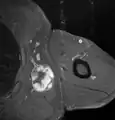

Medical imaging

Medical ultrasonography and magnetic resonance imaging (MRI) of liposarcomas are helpful and often essential in determining their extent, surgical accessibility, and relationship to any observed organ dysfunctions. Since ultrasonography is usually unable to distinguish a liposarcoma from a benign lipoma, MRI is the initial imaging of choice to provide evidence relative to making this distinction.[67]

In myxoid liposarcoma, it shows low signal intensity mass with high signal intensity foci on T1-weighted MRI images. The mass shows high signal intensity on T2-weighted images. This is because it contains predominantly mucoid substance (accounts for low signal intensity on T1) and small amount of mature fat (accounts for high signal intensity on T1).[68] The mass is well-defined, lobulated, multiloculated, or oval in shape without any infiltration into surrounding structures.[68]

Fig. 7 MRI of myxoid liposarcoma of high grade, in the left axillary region of 40-year-old man, highlighted by its white color, in this horizontal section of the tumor.